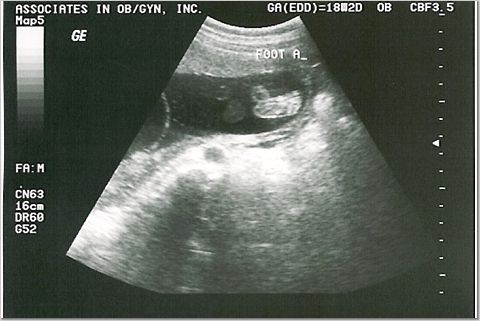

18 weeks - 7 & 8 ounces

We were supposed to find out the sexes, but they were too active for the tech to see!

One of the dancing feet...how cute!